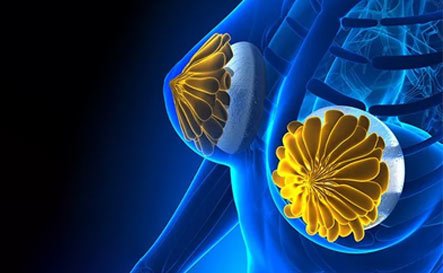

Cosmetic Procedures

Breast Augmentation

Facelift